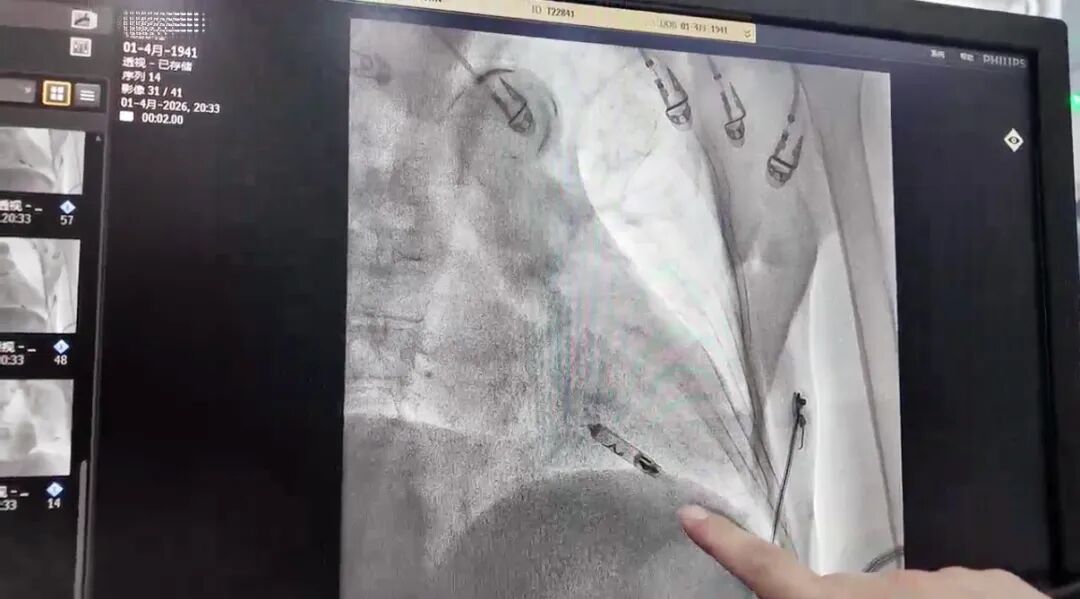

该起搏器体积如胶囊,重量不足2克,无需开胸和切口,仅通过股静脉微小针孔即可植入心脏。

手术由心内科团队精准操作,数十分钟完成,起搏参数正常。术后老人恢复迅速,无并发症,次日即可下地活动,平安出院返回医康养中心,实现了微创救治、快速康复与康养的无缝衔接,体现了医康养融合守护高龄老人“心”生命。